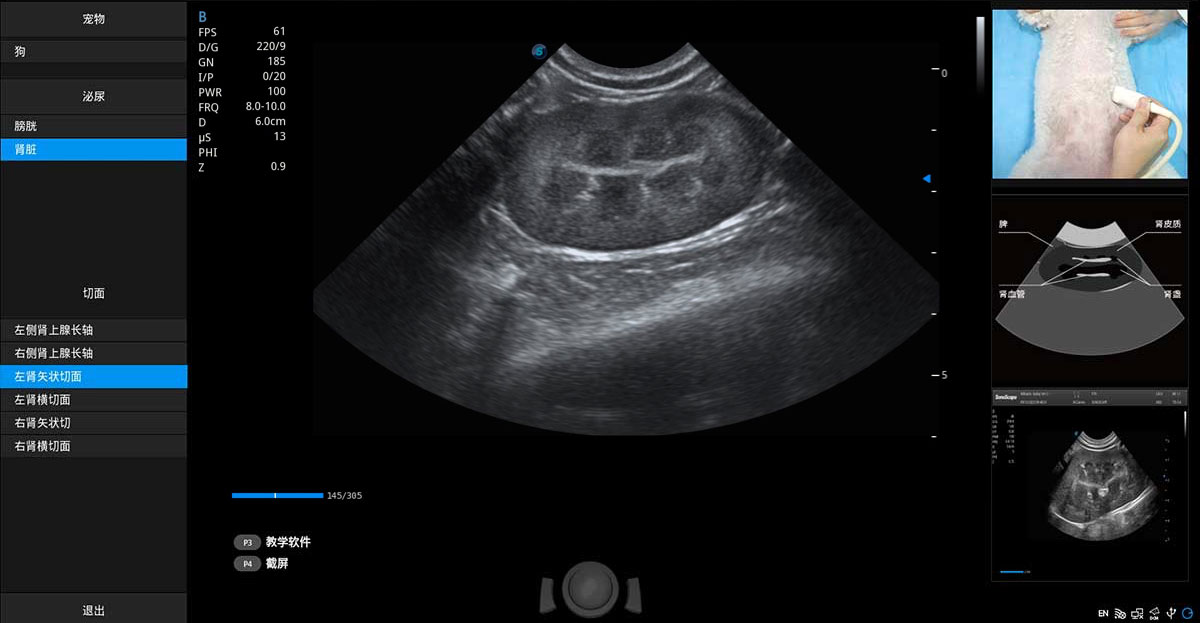

提供解剖示意圖、標(biāo)準(zhǔn)超聲圖像、掃查手法涂和操作者實(shí)時檢查圖像,指導(dǎo)操作者進(jìn)行標(biāo)準(zhǔn)切面的正確掃查。